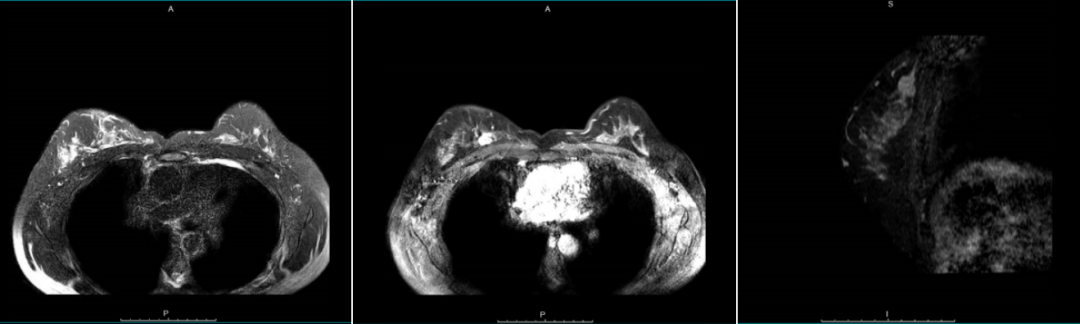

2021年6月9日乳房MRI:双侧乳腺小叶增生,双侧乳腺散在多发T1稍高信号结节,无明显异常强化;右乳上区靠内侧见多发斑片异常信号影,最大者27*21mm,T1WI抑脂呈稍高信号,T2WI抑脂稍高信号,轻度强化。

结论:右乳内异常信号影,考虑BI-RADS 4C

图4乳房MRI